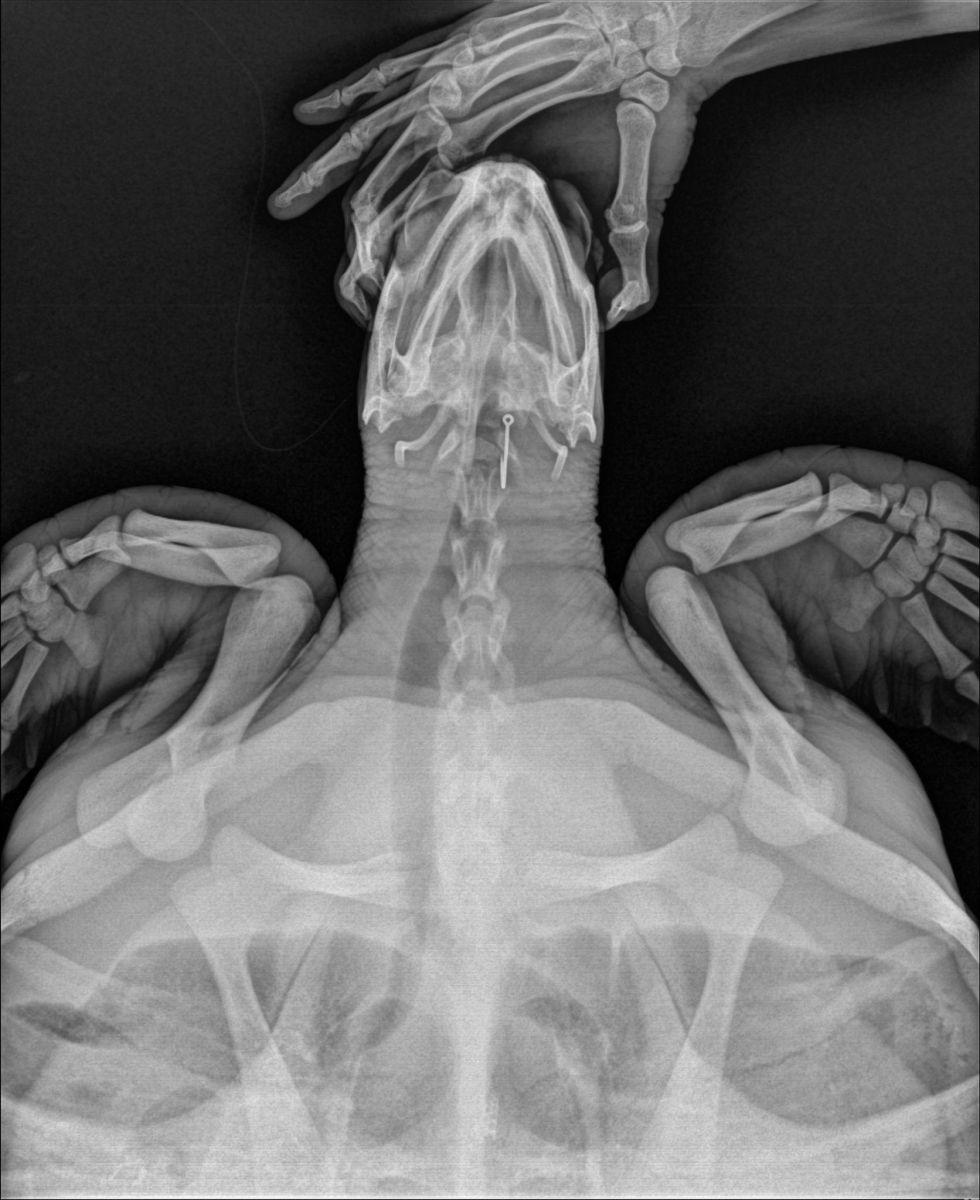

เจ้าหน้าที่ทำการตรวจร่างกายพบเป็นเต่าตนุ (Chelonia mydas) อยู่ในช่วงวัยรุ่น ขนาดกระดองกว้าง 50 เซนติเมตร ขนาดกระดองยาว 53 เซนติเมตร น้ำหนักประมาณ 17.5 กิโลกรัม ความสมบูรณ์ของร่างกายอยู่ในระดับสมบูรณ์ปกติ (BCS 3/5) สภาพภายนอกไม่พบบาดแผล มีเพรียงขนาดเล็กเกาะบริเวณกระดองท้อง สภาพร่างกายแข็งแรง ตอบสนองดี ตรวจพบเส้นเอ็นติดอยู่ที่บริเวณช่องปาก สัตวแพทย์ได้ทำการตรวจร่างกายโดยการถ่ายภาพรังสี พบเบ็ดตกปลาติดอยู่ภายในช่องปาก 1 ชิ้น